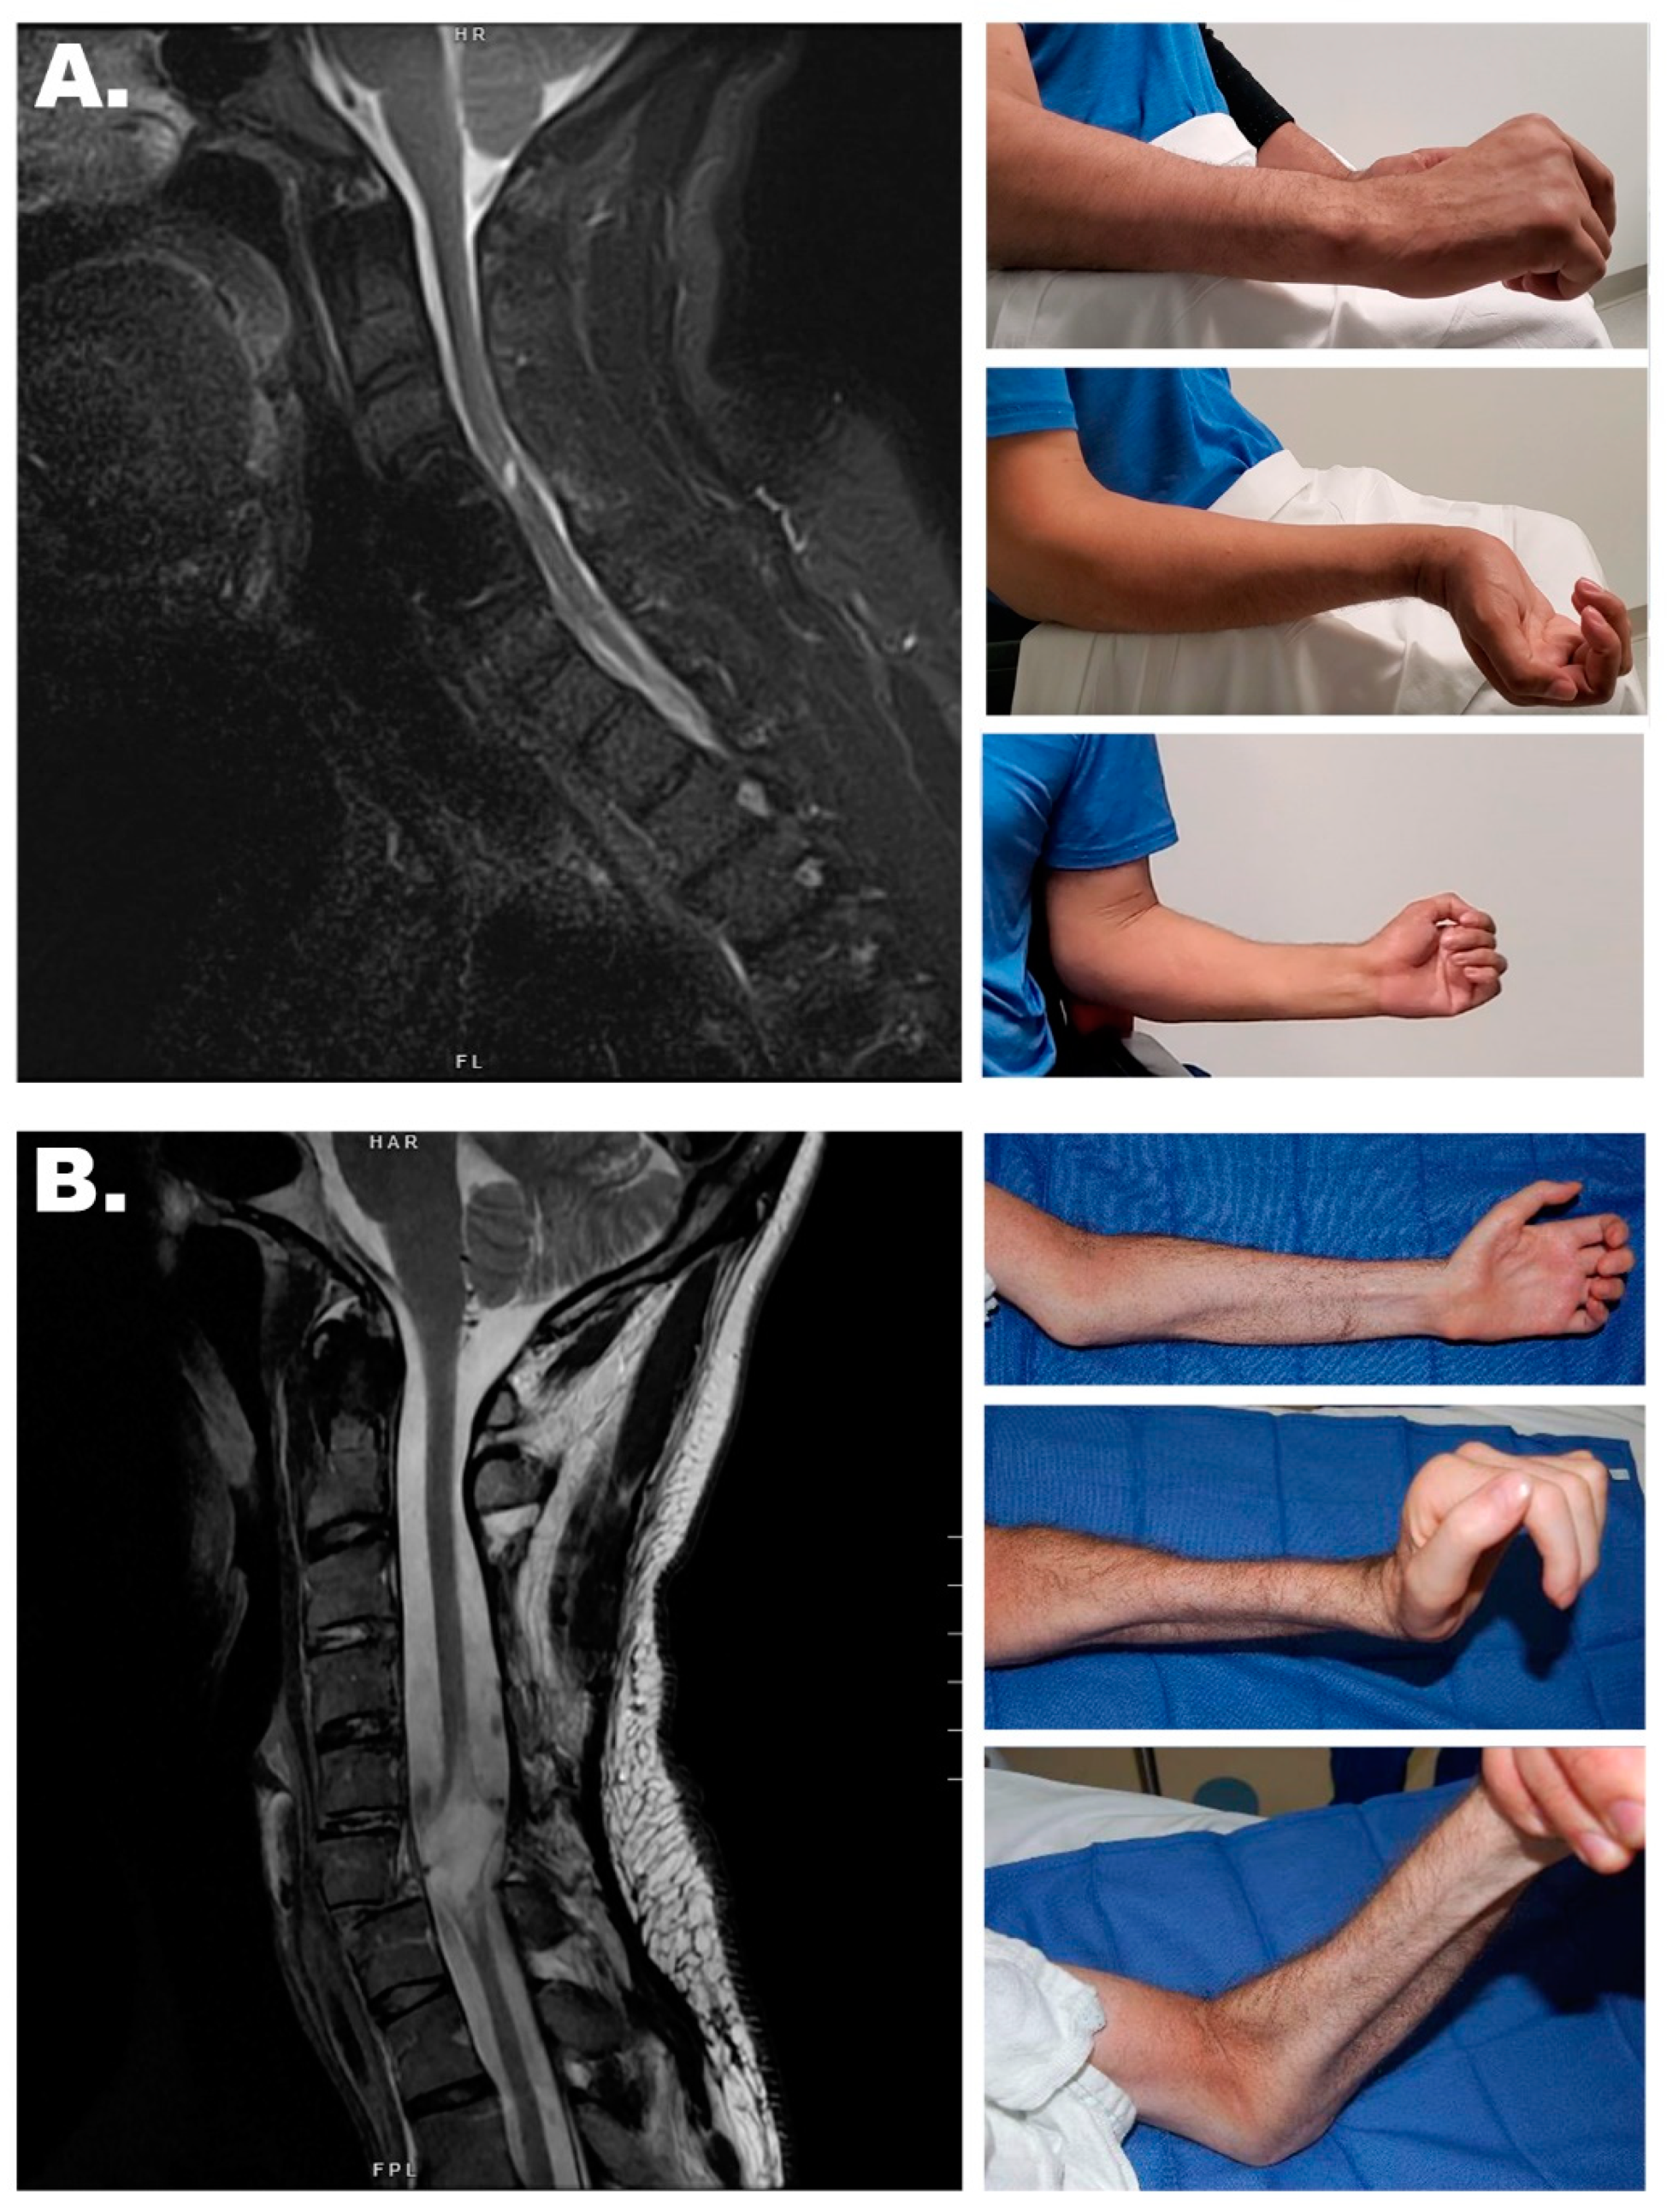

3.1. Nerve Transfers

Sensory Preservation